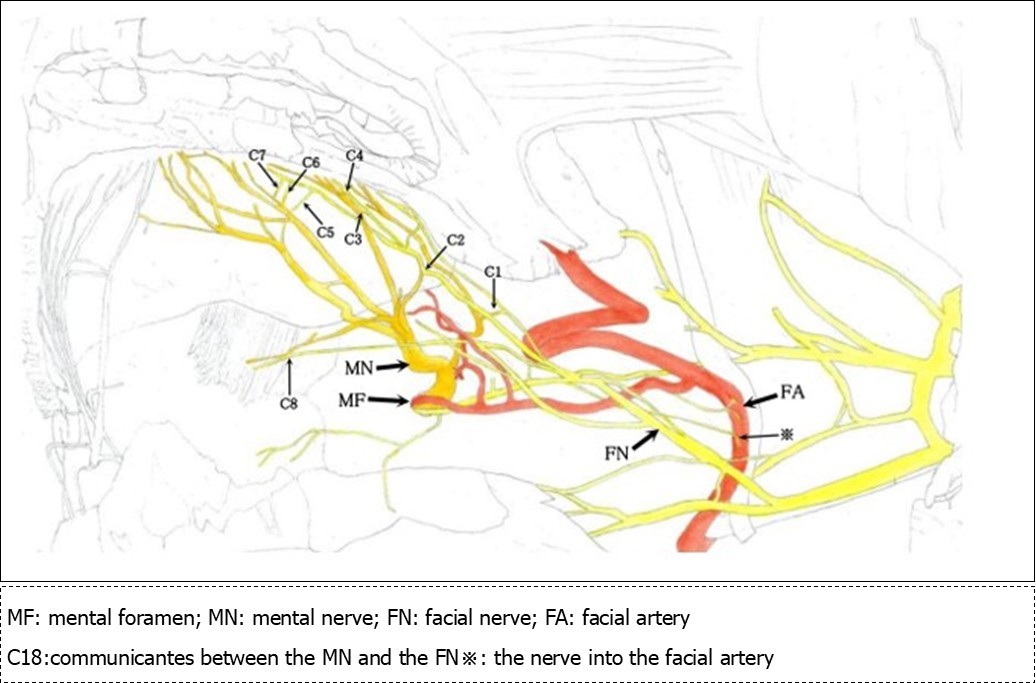

Figure 2.Sketch of the mental nerve, marginal mandibular branch of the facial nerve and the facial artery

The various branches of the mental nerve belong to a communicating branch that joins with the marginal mandibular branch of the facial muscle. In addition, a relatively thick branch of the marginal mandibular branch of facial muscle communicates with the inferior arterial arch of the alveolar artery and the facial artery at the mental foramen. This characteristic was similar among all specimens.

Marginal Mandibular Branch of the Facial Artery

Two branches extend from the anterior margin of the inferior corner of the parotid gland. The superior branch runs parallel to the mandibular base, while the inferior branch runs anteriorly along the corner of the mandible, after which (and immediately before encountering the facial artery and vein) it branches off into two branches. The first branch follows the inferior margin of the mandible, and the second branch turns in an anterosuperior direction. The latter of these two passes across the facial artery, vein, and mentalis branch of the facial artery and reaches the lower lip. During its course, at the point immediately after passing over the mentalis branch, it fuses with a the buccal branch of the facial nerve, and the branches that arise from this fusion advance toward the lower lip (2 branches) and mentalis (1 branch), enter the mental foramen (1 branch), and a fine branch (1 branch) runs in a posterior direction toward the facial artery. The branch that moves toward the lower lip is a branch that communicates with the anguli oris branch and inferior labial branch (Figure 2, C1-7). The branch that advances toward the mentalis adheres to the mentalis branch of the mental nerve (Figure 2, C8), and the branch that enters the mental foramen adheres to the inferior alveolar nerve immediately after entering the mandibular canal (Figure 3F). There is one fine branch that branches off from the fusion point and advances toward the facial artery (Figure 2※). Prior to the fusion point, there was a branch that branched off the buccal branch and advanced toward the facial artery. The left inferior labial artery was missing, but a similar feature was observed in all specimens.

Communication between the anguli oris branch and marginal mandibular branch occurred at a point 1.5 cm from the anguli oris and advanced in a posteroinferior direction at a 45-degree angle (Figure 2, C1)

Communication between the inferior labial branch and marginal mandibular branch at the center of the lower lip, which formed at the most inferior portion of the oral vestibule, which was inferior to the anguli oris (Figure 2, C2)

Communication between the inferior labial branch and the marginal mandibular branch at 1 cm from the vermilion border of the lower lip (Figure 2, C3-7)

Communication between the mental nerve and marginal mandibular nerve inferior to the mentalis muscle (Figure 2, C8)

Communication between the inferior alveolar nerve main trunk and the marginal mandibular branch immediately following entrance into the mandibular canal from the mental foramen (Figure 3, F)

The Origin of the Nerves that Compose the CommuniCating Branches and the Types of Nerve Fibers

Based on the results obtained in this study, the mental nerve and the marginal mandibular branch of the facial nerve are completely fused at the perineurium. Most nerve diagrams indicate that the mental nerve is only a sensory nerve, and that the marginal mandibular branch of the facial nerve is a pure motor nerve. However, we found that there is a need for autonomic nerves to be present in the lower face region, where there are salivary glands and sweat glands, including the lower lip and chin (the regions of these nerves). Hence, we aimed to determine where these nerves originate. In the present study, we observed that the vasomotor nerve of the facial artery branched off from the buccal branch and the marginal mandibular branch of the facial nerve (Figure 2※), and we identified the fact that there are sympathetic and parasympathetic fibers in the facial nerve. This was also confirmed micro-anatomically. Figure 5 shows a cross-section of the optic nerve, and Figure 6 shows a cross-section of the mental foramen region of the mandibular nerve. Tyrosine hydroxylase immunostaining stained the sympathetic nerves (provided by lecturer Masahito Yamamoto of the Department of Anatomy, Tokyo Dental College). The trigeminal nerve includes sympathetic fibers, and when the two sections are compared, the optic nerve has a substantial number of such fibers, whereas the mandibular nerve has very few. Matsubayashi 10 wrote extensively on this issue. It is known that the trigeminal nerve, which is the great auricular nerve, auriculotemporal nerve, and zygomatic branch of the facial nerve, consists of cutaneous nerves of the face and sympathetic nerve fibers, although there are few sympathetic nerve fibers in the maxillary nerve or mandibular nerve.

Normally, the mental nerve and facial nerve have intercommunicating branches (Figure 2, all references).

There are vasomotor nerves in the marginal mandibular branch of the facial nerve, which includes autonomic nerves (Figure 2)